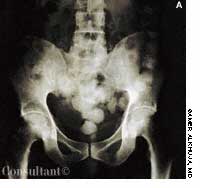

This rash, which covered a 68-year-old woman's body, was noted to have worsened during the past 2 months. A cephalosporin antibiotic had failed to clear the condition. The patient, a nursing home resident, suffered from emphysema, asthma, and heart disease. She had been receiving oxygen therapy and prednisone for 1 year.